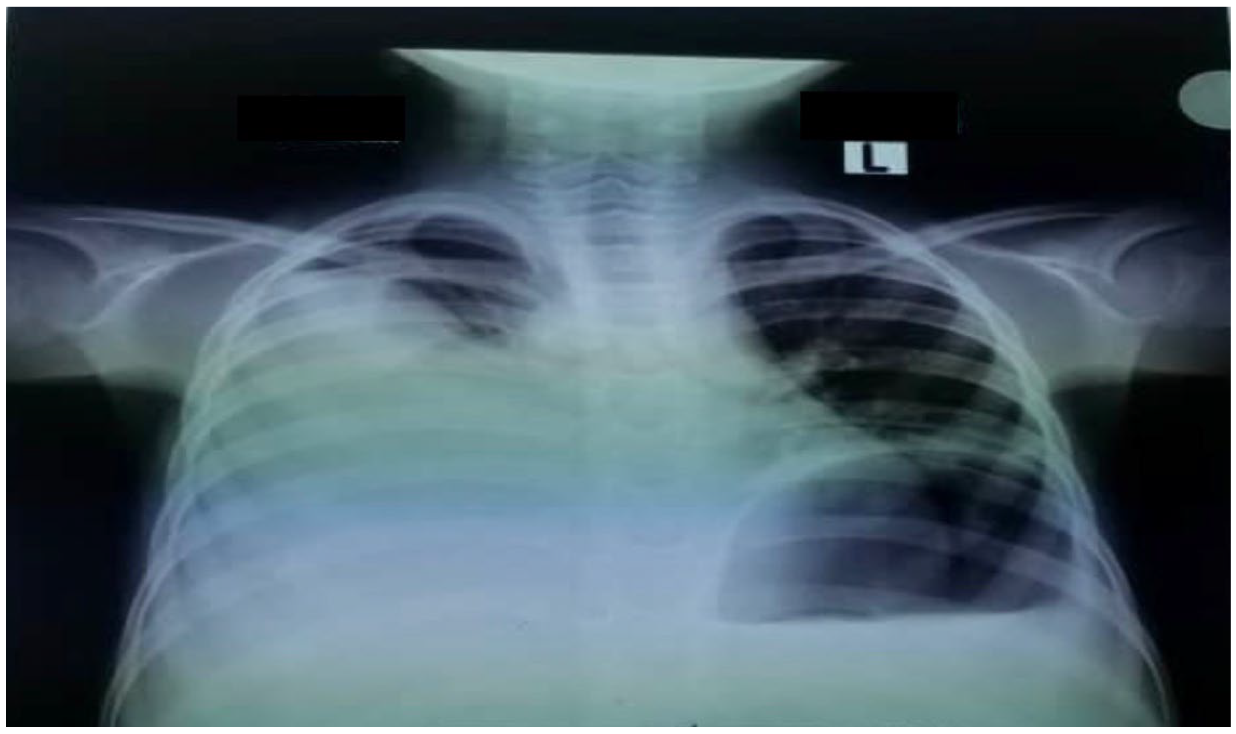

In addition to starting broad-spectrum antibiotics (IV ceftriaxone 1 g daily and vancomycin 40 mg/kg daily) for suspicion of bacteria coinfection and IV electrolyte replacement and fluid resuscitation with normal saline infusion, an abdominal CT scan was performed, which revealed a large cystic mass (possibly a urinoma) on the left kidney with hydronephrosis and moderate ascites (Figure 3).

Figure 3. A cross-sectional view of the abdominal CT scan showing large left renal cyst (red arrow) with hydronephrosis.